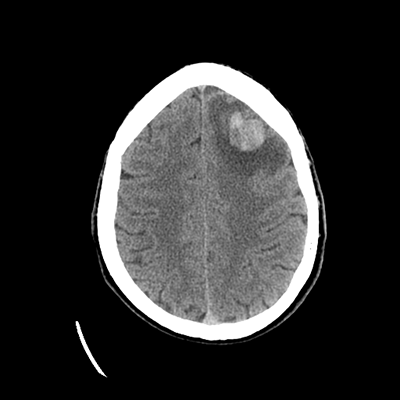

A 51 year-old man with metastatic RCC (diagnosed in 2010, previously on ipilimumab/nivolumab, now on cabozantinib since 2022) with known multifocal brain metastases c/b symptomatic focal epilepsy (on levetiracetam) initially presents to the ED due to subacute progressive gait difficulties. He's been experiencing some unsteadiness and weakness of his left leg. He does require use of a cane, but he hasn't had any falls. His last seizure was one year prior; he's had none since his levetiracetam was increased to 1.5g bid.

In the ED, he undergoes a non-contrast head CT. You are then consulted.

NCHCT